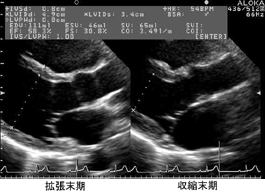

立位心や肺疾患がある症例では左心室が斜めに描出されることがある。

この場合は無理なMモード計測はせずBモード法で左室径及び左室容積の推定をするのが望ましい。